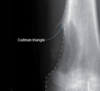

Tríangulo de codman típico del osteosacroma

60